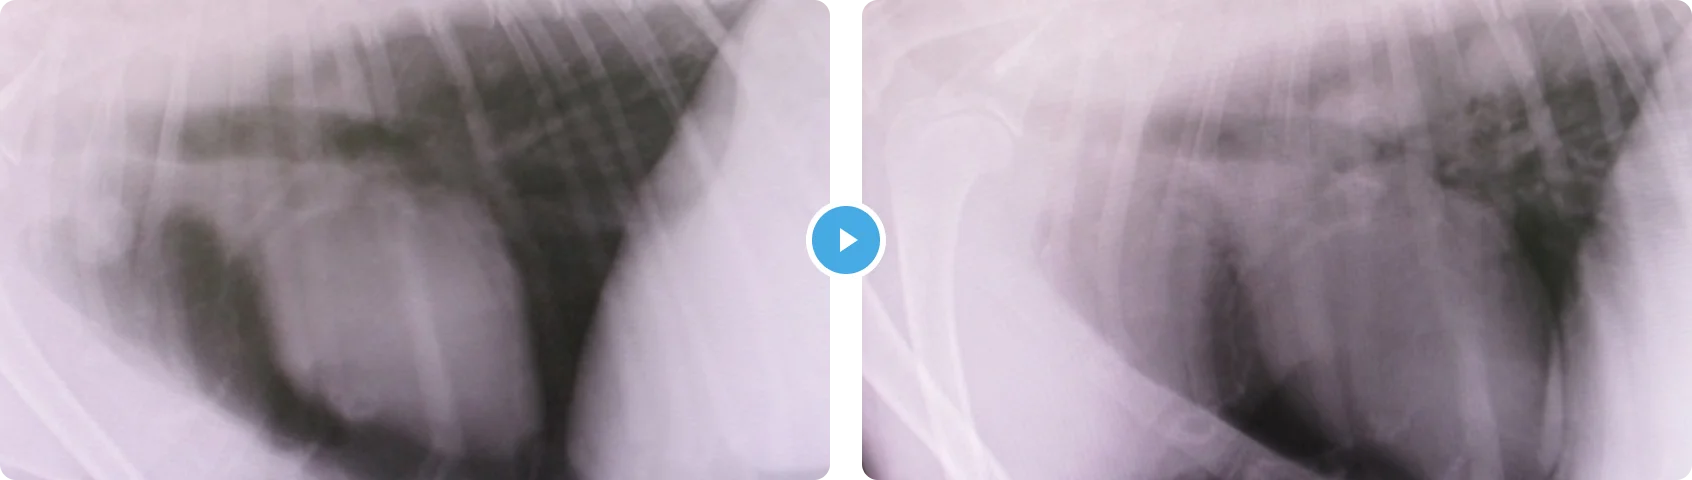

はいがん(はいししょうこうぐん) 肺癌(肺指症候群)

- 症状の説明

- 治療の内容

身体検査からは左前肢の爪に出血があり、爪の根元が腫れていました。その他、本人には症状がなく元気とのことでした。ただ爪をみると単なる外傷でなく見えたので、爪先の細胞診検査とレントゲンを撮りました。

その結果、爪の根元からはやや異型性のある上皮性系の細胞が採取され、肺には腫瘤がみられました。以上の所見より、「肺癌の爪先転移による跛行」と診断しました。

未分化な腫瘍細胞は血流にのり、指先でつまるのかそこに転移病変を作ることがあります。肺指症候群といわれ、予後の悪い肺癌といわれています。残念ながら、治すことは難しいため、痛みの緩和と苦しくなったら酸素吸入での対処をしていきました。